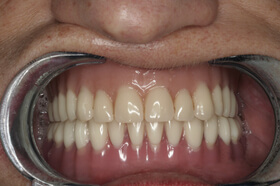

A végeredmény, a frontfogak a belső oldalon összesínezve